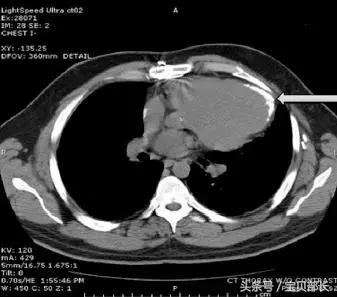

空气进入血管之后

确实会顺着血管进入心脏

然后

会发生两种情况

一种少量空气,啥事没有

一种大量空气,会形成“气栓塞”